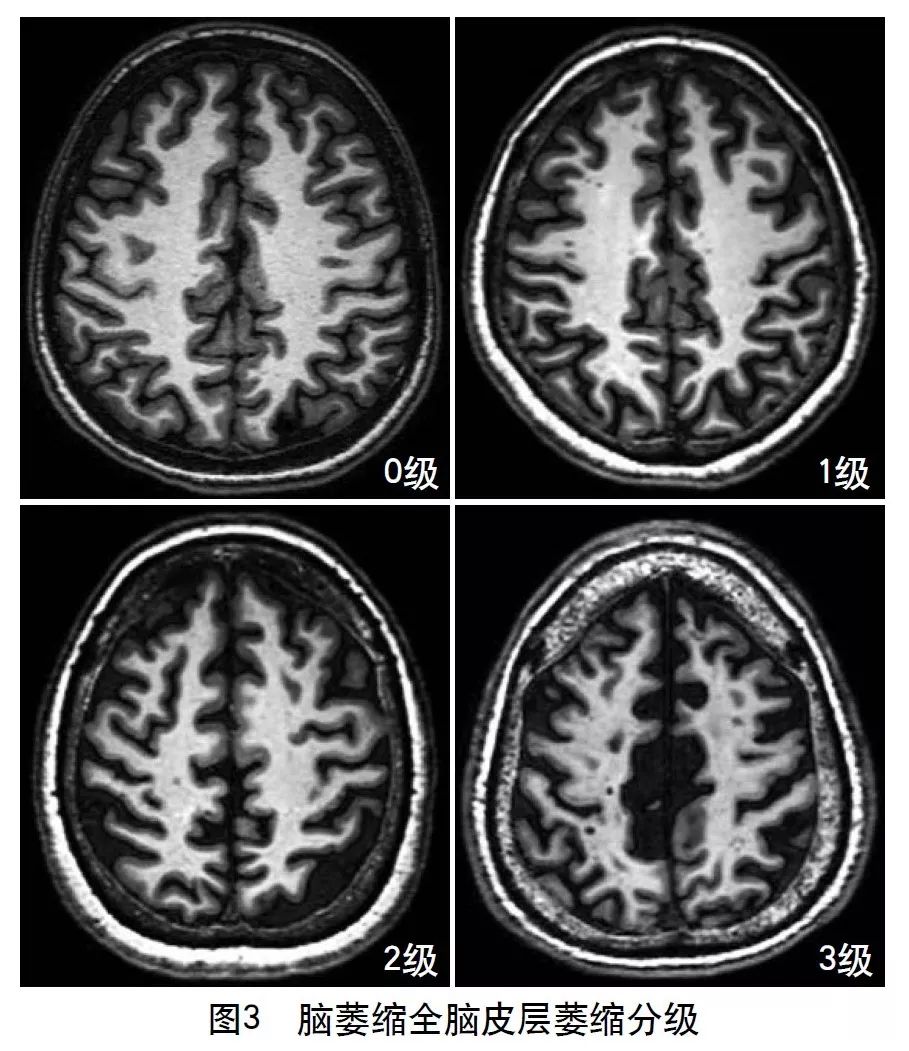

2013年的共识指南将脑萎缩定义为与特定的局灶性损伤,如脑外伤或脑梗死无关的脑容积减少。脑萎缩可以是广泛的或局部的(如特定的脑叶或海马等特定区域),可以是对称或不对称的,亦可以是组织选择性的(如发生在白质等某一特定组织层)。目前不同部位的脑萎缩有相应的诊断标准,全脑皮层萎缩分级用于评价全脑(图3);内侧颞叶萎缩分级主要评价颞叶内侧,重点是海马(图4);Koedam分级主要评价顶叶,尤其是扣带回和楔前叶(图5);Kipps/Davies分级主要评价额颞叶(图6)。推测脑组织减少是由脑沟(周围)和脑室(中心)的脑脊液空间相对于颅内容积扩大所引起的。